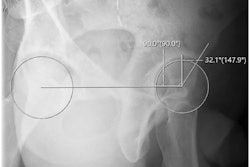

In this study, Paolucci and colleagues evaluated the safety and efficacy of lateral circumflex femoral artery (LCFA) embolization in seven patients. The patients (ranging in age from 45 to 84) had chronic pain, were unresponsive to conservative treatments, and had clear signs of advanced osteoarthritis on MRI scans.

Image courtesy of the ECR.